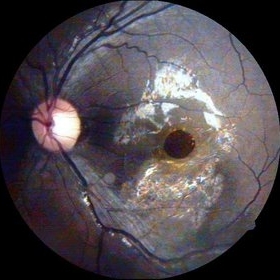

Optic Nerve Head Avulsion

Sep 15 2014 by Mehul A Shah

A 30-year-old male presented with loss of vision following blunt trauma.

Photographer: Drashti Netralaya,Dahod

Imaging device: Zeiss ff450

Condition/keywords: optic nerve head avulsion